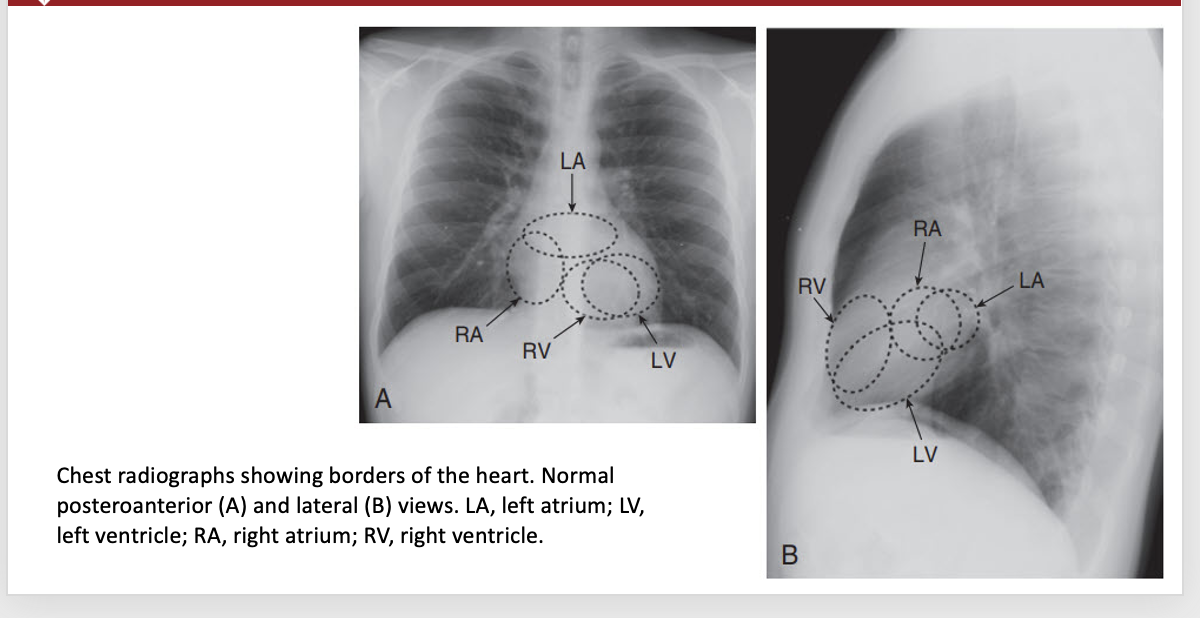

Chest radiographs with borders of the heart